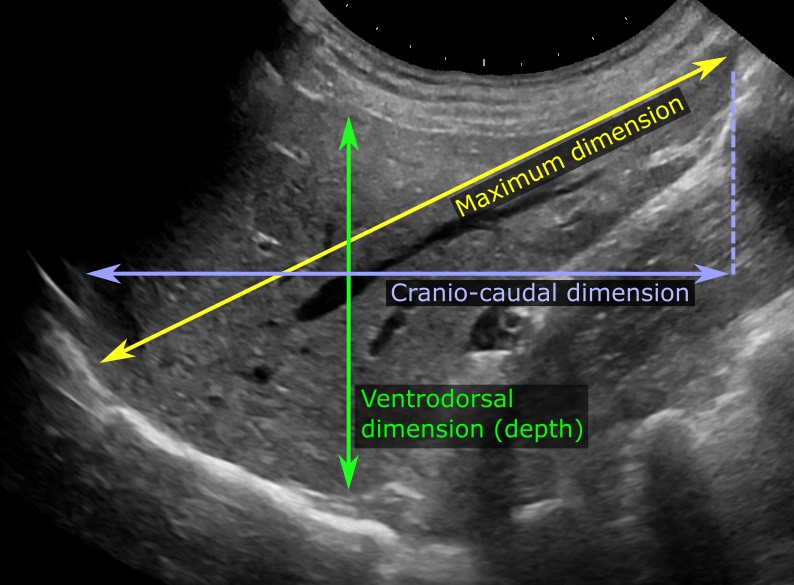

Medidas para avaliação do tamanho do fígado na ultrassonografia

Em exames de imagem não fica mais fácil. Na falta de um método prático de calcular o volume, exames de imagem medem o fígado de vários ângulos, o que nem sempre é possível e pode levar a outros tipos de erros. Um erro comum, por exemplo, é quando o fígado tem uma variação anatômica (normal) chamada “lobo de Riedel“. Trata-se de um prolongamento afilado da borda inferior do lobo direito do fígado que ocorre em uma média de 17% das pessoas (e três vezes mais comum em mulheres do que em homens) que nem sempre é fácil de identificar no exame físico mas frequentemente é interpretado como hepatomegalia por ultrassonografistas que levam em consideração apenas a extensão do fígado.